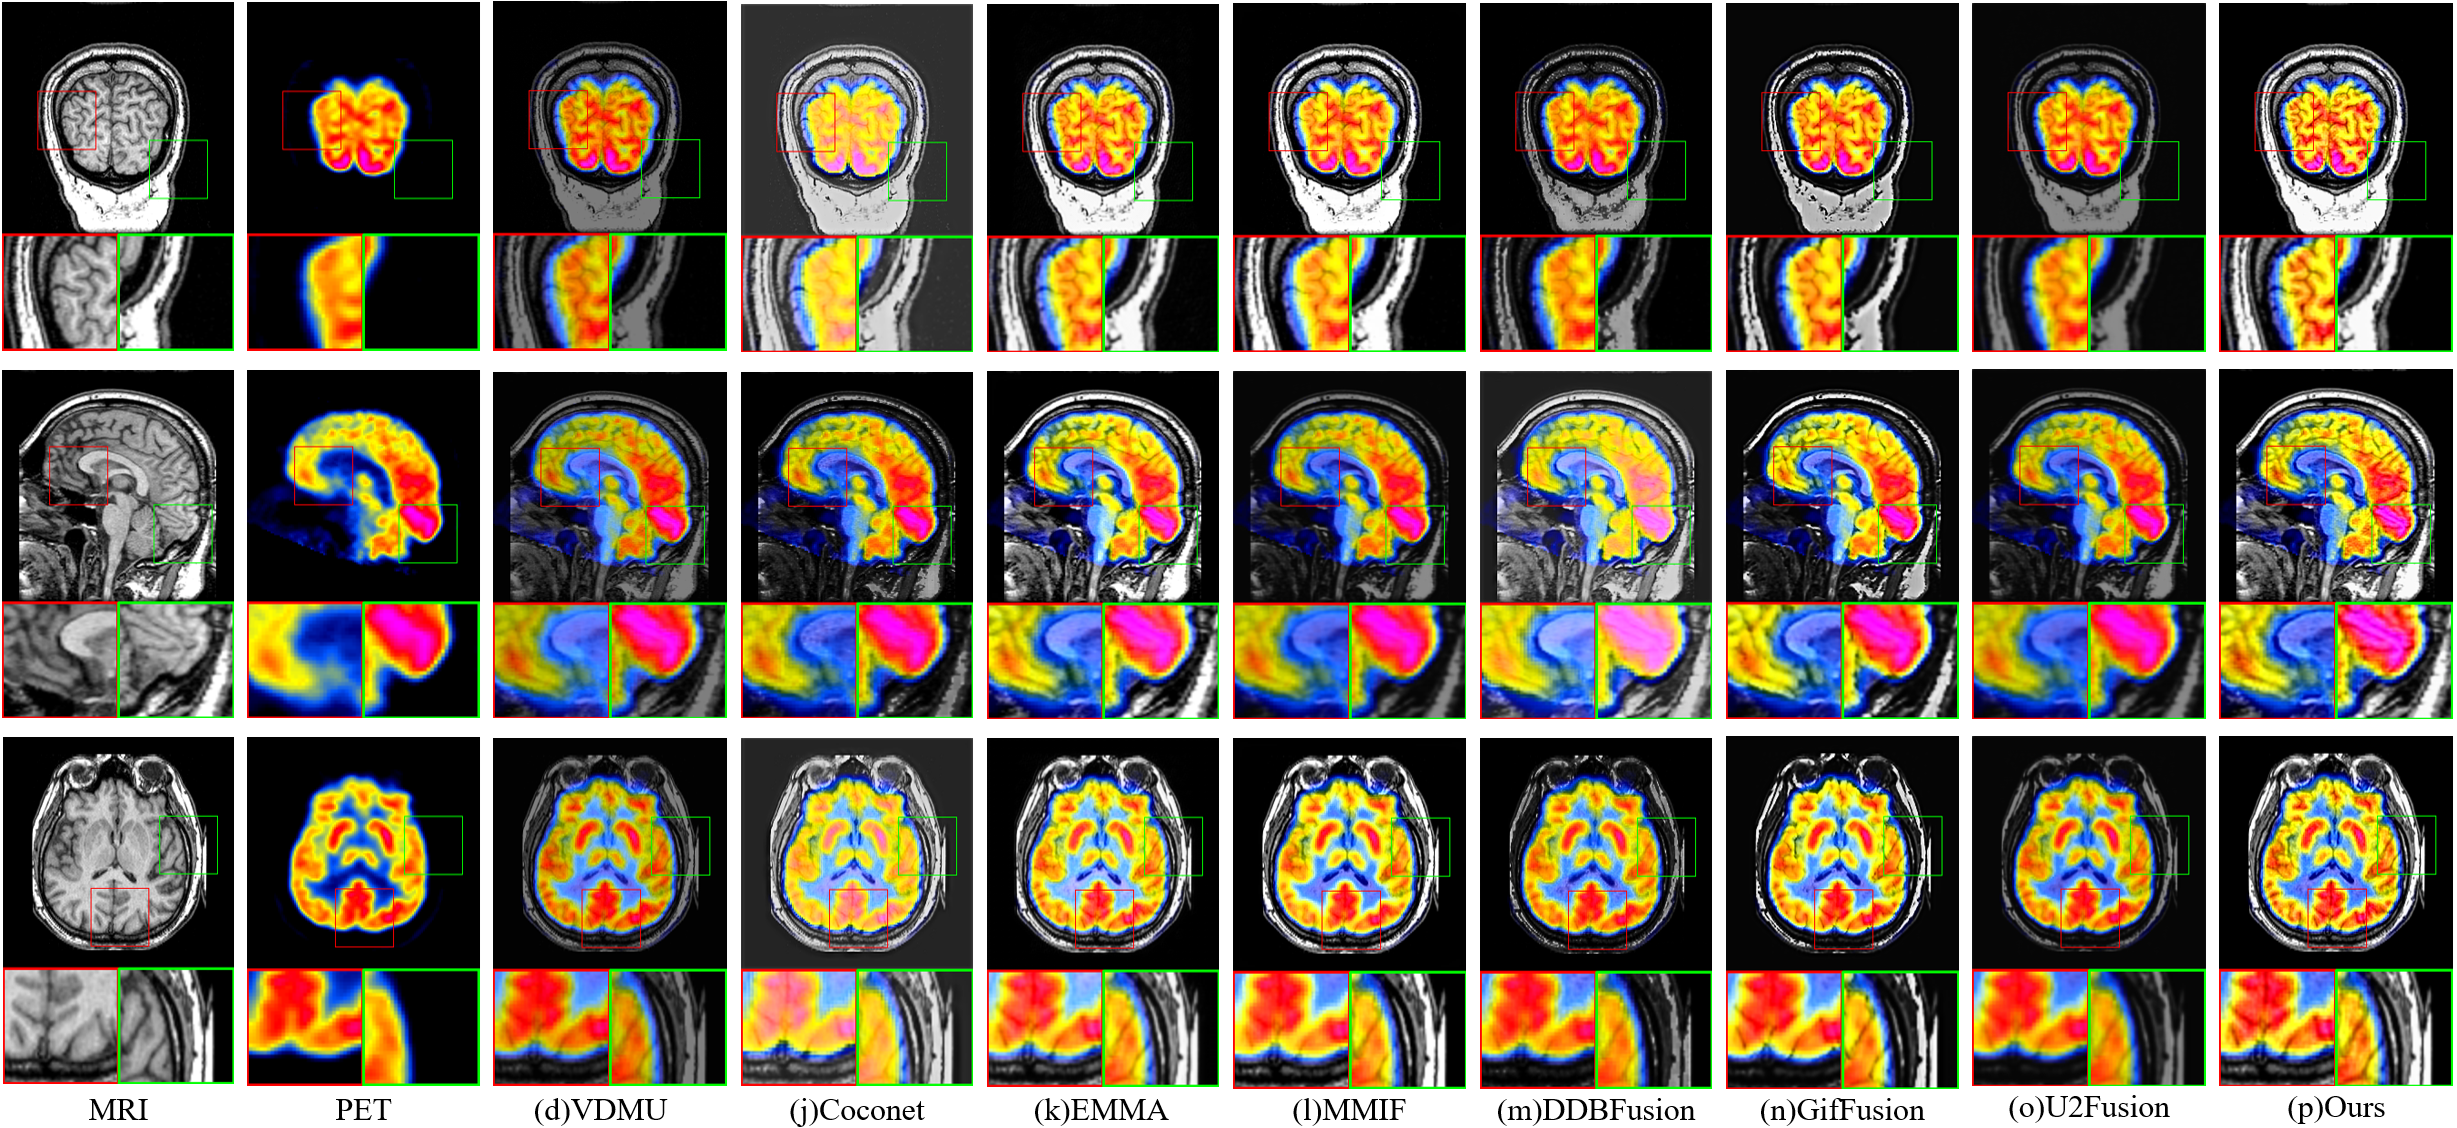

IV-B2 Medical image fusion

Figure 7 shows the fusion results produced by different methods, and for clearer observation, the regions rich in details are further enlarged. From the magnified regions of the fused images, we can observe that our method effectively preserves the color characteristics of the PET images while maintaining the complex structural details. The edges in the MRI images are also well preserved during the fusion process, which verifies the effectiveness of our method. As shown in Table II, our method achieves the best or second-best performance across all objective metrics, demonstrating its overall effectiveness.

Refer to caption

Figure 7: Qualitative comparison of fused results obtained by different methods on the MIF task.